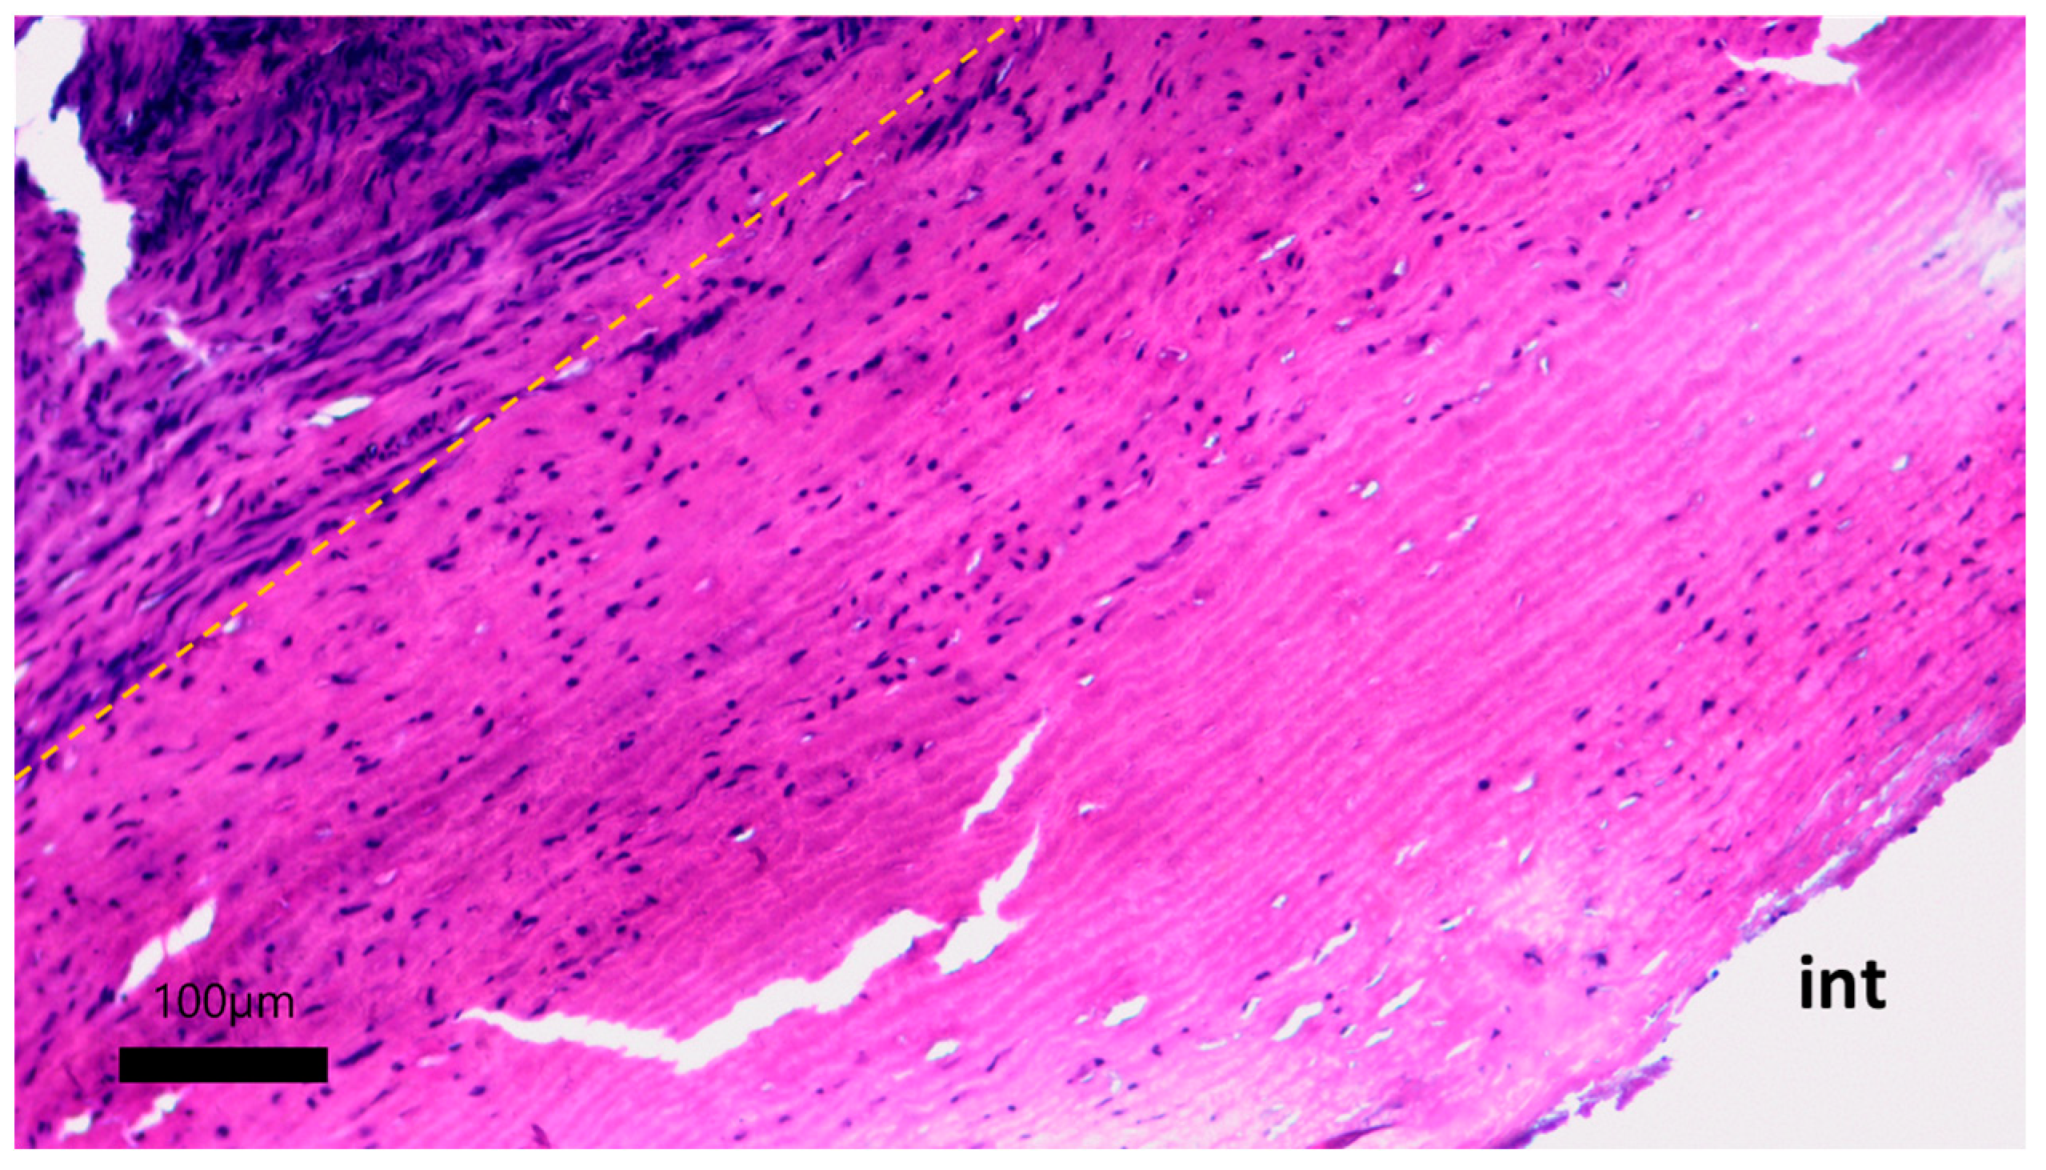

The formation of a neointimal layer is noted directly in the anastomosis zones with further spread to the tissue of the vascular graft. Laser treatment did not have a negative effect on the permeability of the vascular graft wall for fluid. Microscopic examination of the developed vascular prostheses after 30 days of implantation in pigs revealed the initial stages of colonization of the cell-free stroma of the graft with fibroblast-like cells (Figure 12).

On the micrographs, there were no zones of inflammation with foci of lymphocytic infiltration, and no signs of thrombus formation on the surface of the vascular graft were found. The tissue of the prosthesis does not differ in its structure from the original one: the packing of collagen fibers is dense, the waviness of the elastic fibers is not disturbed, and no zones of loosening were found. The stroma of the graft is populated by small fibroblast-like cells (Figure 13).

Figure 12. Cellular migration into the stroma of the vascular prosthesis: hematoxylin–eosin staining, scale bar 100 μm. Yellow dotted line—the boundary of the implanted vascular graft and the newly formed adventitial tissue; int—intimal side of the vascular graft.